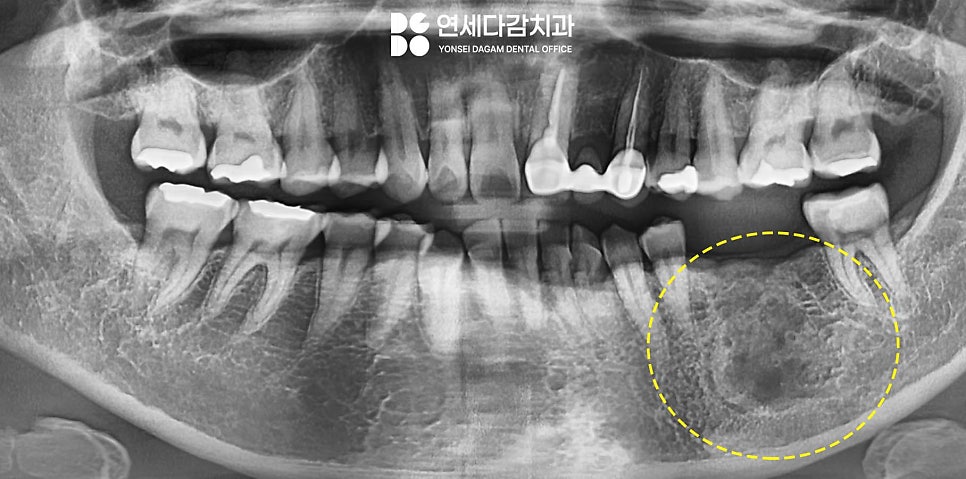

해당 케이스는 발치 후

법랑모세포종을 제거하였습니다.

안전 변연을 포함한

뼈 일부를 함께 제거하게 되면

뼈이식을 통해 턱뼈 재건을 하기도 합니다.

1개월 정도 확실한 회복을 통해

뼈가 안정되면,

임플란트를 통해 결손된 부위를

회복할 예정입니다.